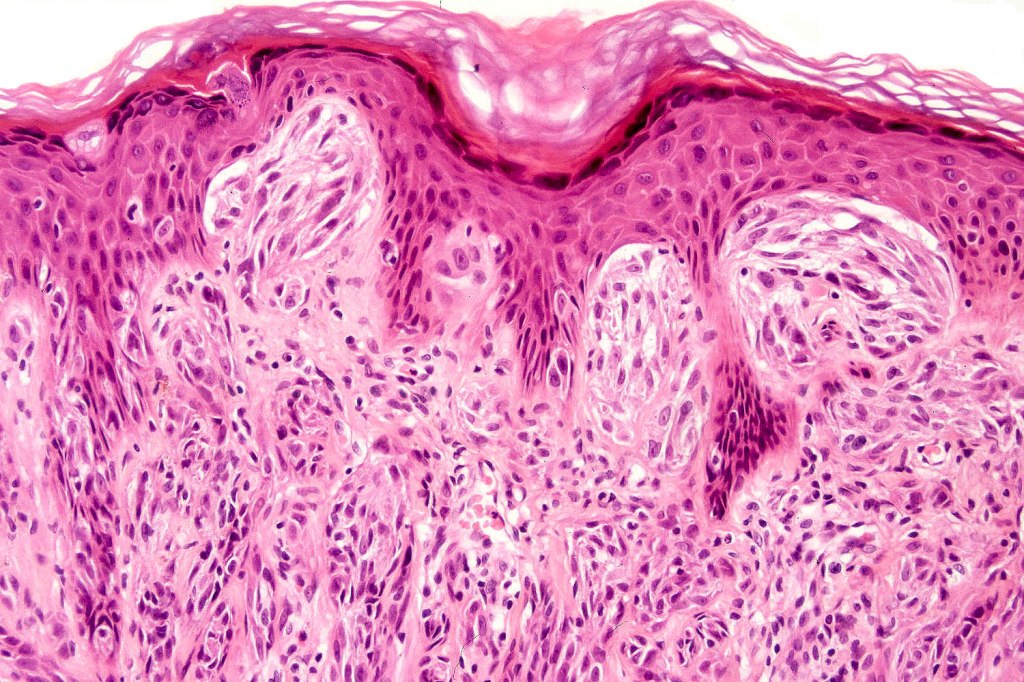

•Hyperkeratosis & acanthosis, sometimes very marked

•Pseudoepitheliomatous hyperplasia

•Junctional nests often vertically orientated, dyscohesive with a surrounding retraction artifact

•Kamino bodies (often multiple) are a characteristic feature